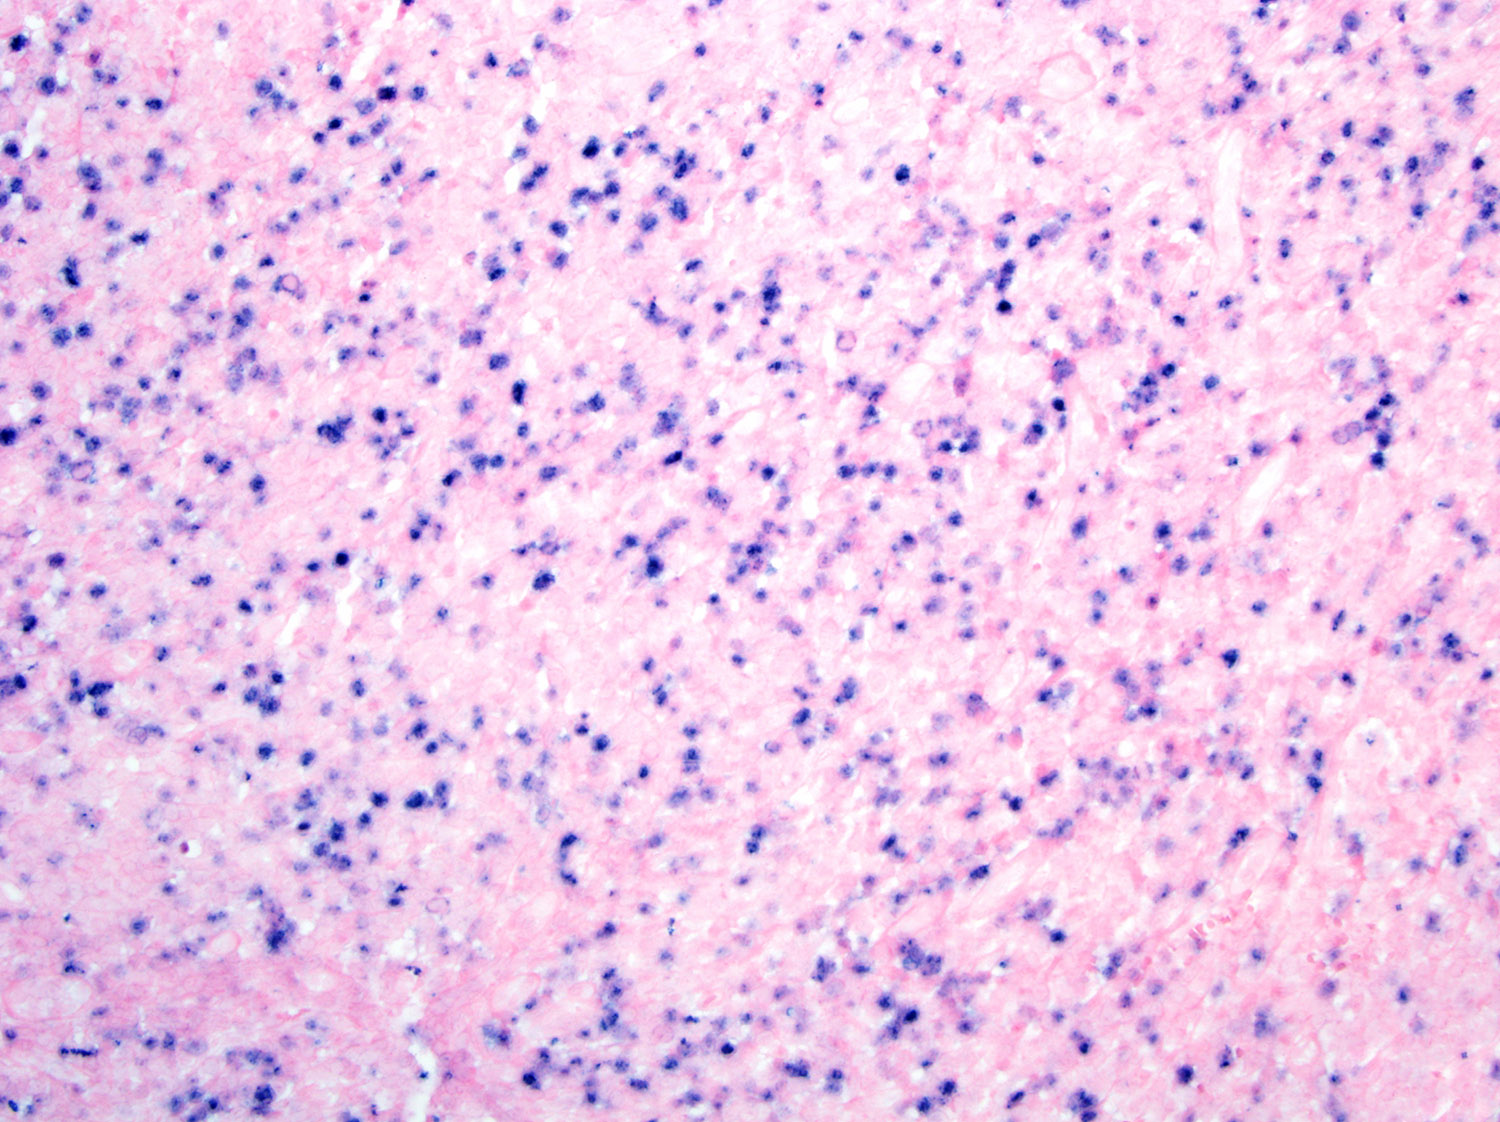

人気商品の再入荷情報をお届け! Diagnostic Pathology: Lymph Nodes and Extranodal Lymphomas | ScienceDirect 洋書

人気商品の再入荷情報をお届け! Diagnostic Pathology: Lymph Nodes and Extranodal Lymphomas | ScienceDirect 洋書

Diagnostic Pathology: Lymph Nodes and Extranodal Lymphomas | ScienceDirect,

Diagnostic Pathology: Lymph Nodes and Extranodal Lymphomas | ScienceDirect, Diagnostic Pathology: Lymph Nodes and Extranodal Lymphomas: 9780323847582: Medicine & Health Science Books @ Amazon.com,

Diagnostic Pathology: Lymph Nodes and Extranodal Lymphomas: 9780323847582: Medicine & Health Science Books @ Amazon.com, Pathology Outlines - Extranodal NK / T cell lymphoma,

Pathology Outlines - Extranodal NK / T cell lymphoma,旧蔵 清代 中国の占術 中國古代占い風水 線裝 符録秘訣 古本 中国古書 古文書 唐本 中国古美術 漢籍 古典籍 風水学 開運 唐物 希少 RS07